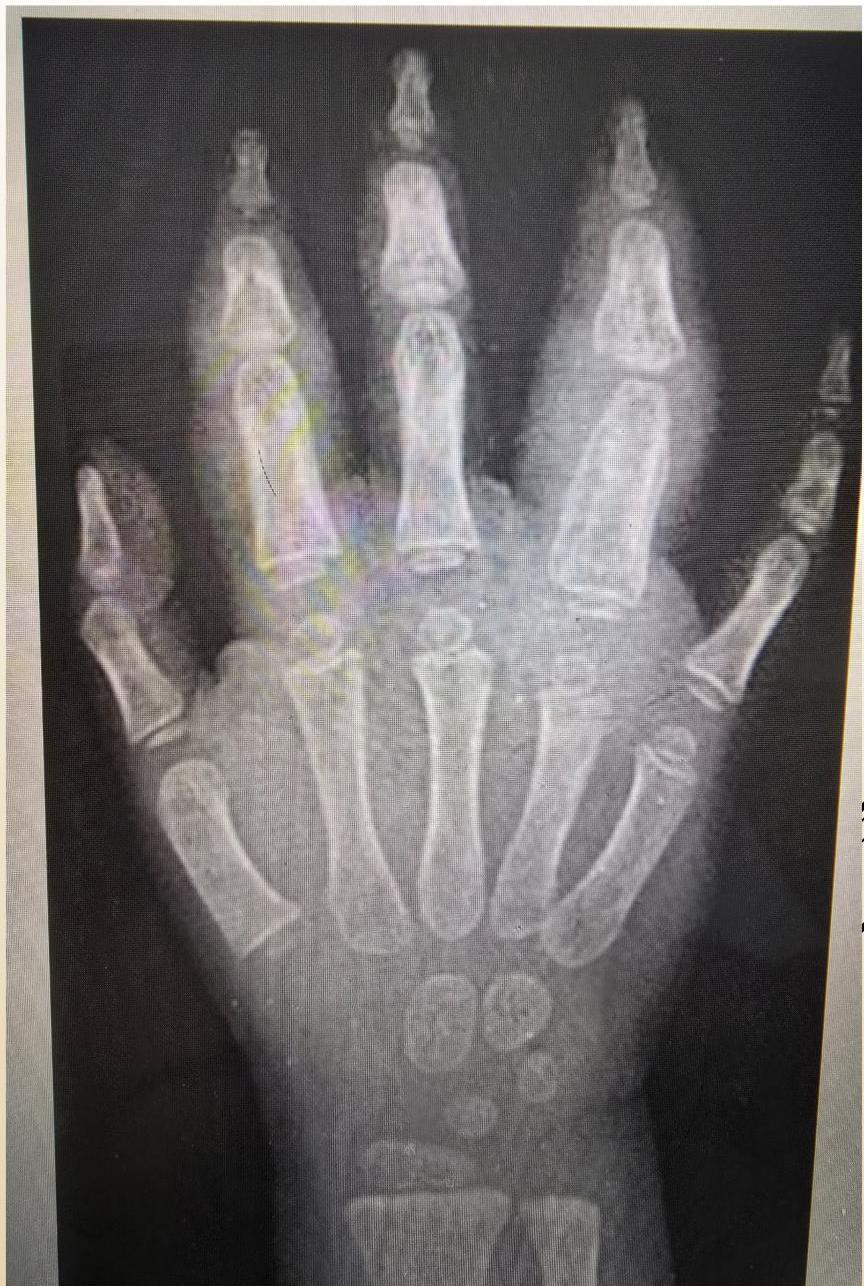

Imaging Findings (sJIA)

Early radiographic changes (6 month duration): Soft tissue swelling and periosteal new bone formation appear adjacent to the second and fourth proximal interphalangeal joints.

Radiographic Progression (Examples)

Hand Progression: A: Radiograph at onset. B: 4 years later - Loss of articular cartilage, destructive changes in distal/proximal interphalangeal and metacarpophalangeal joints, destruction and fusion of wrist bones.